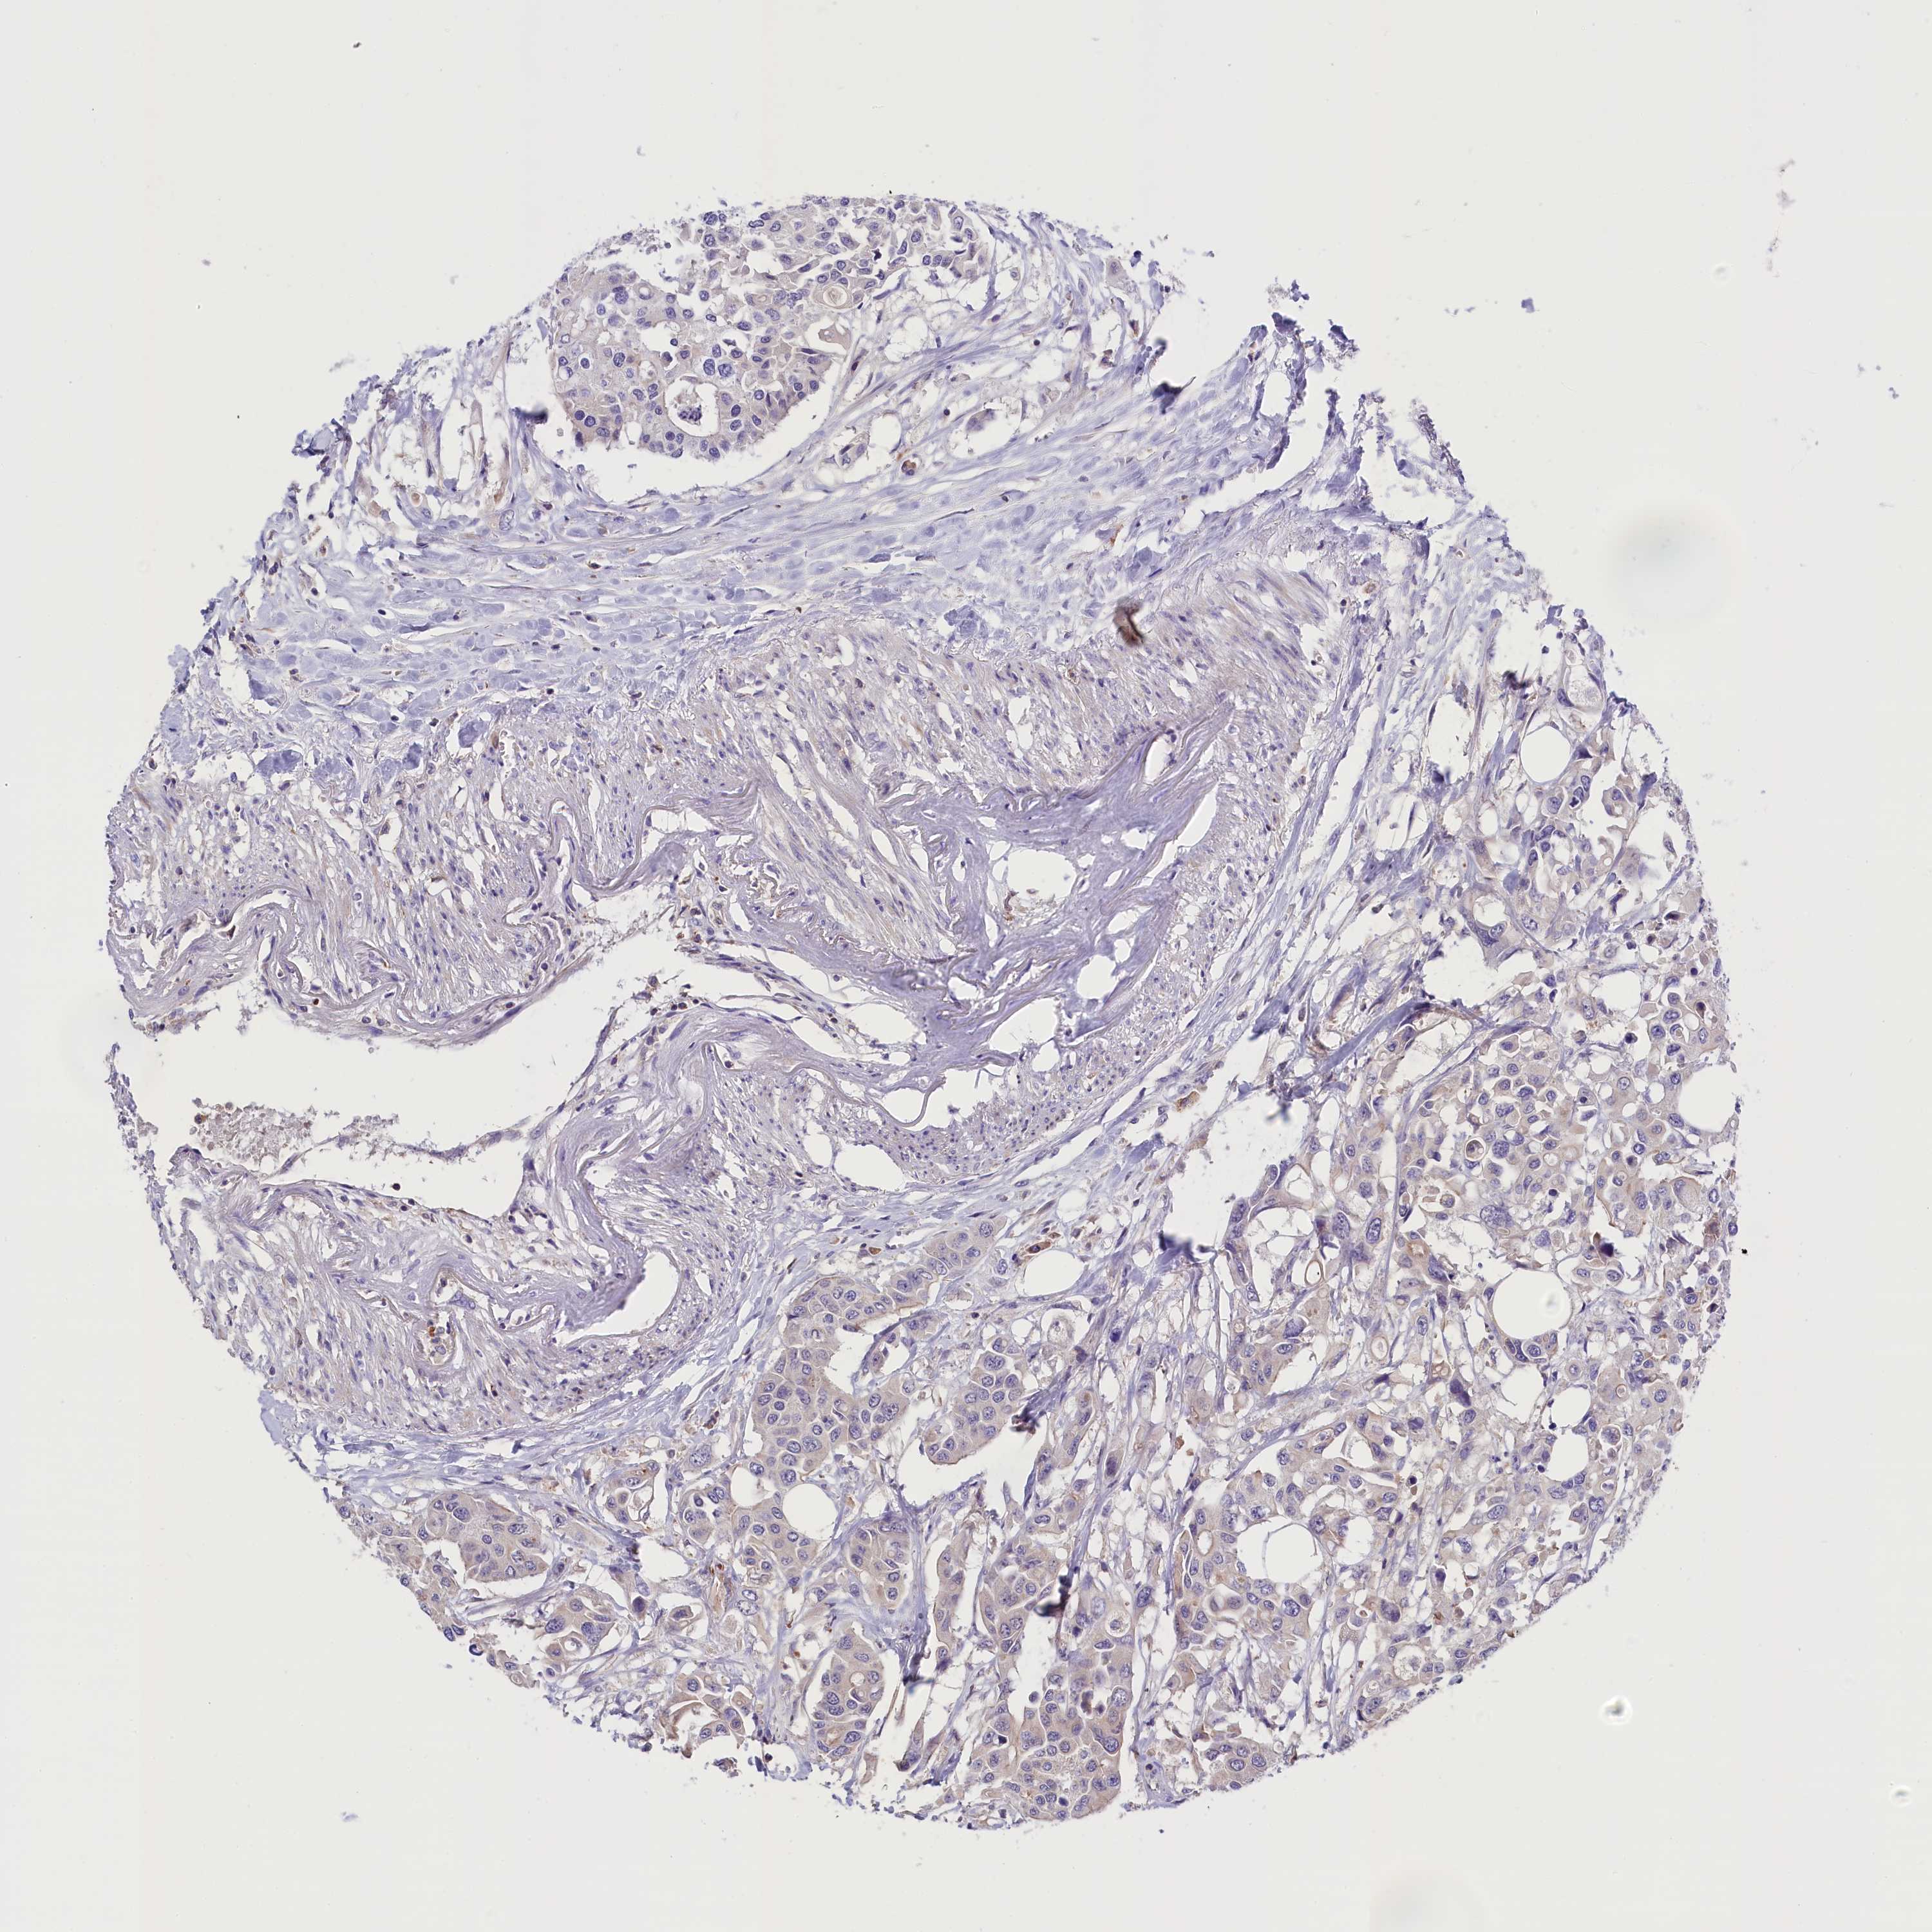

CANCER COLORECTAL CANCER Show tissue menu

Colorectal cancer

Human cancer

Colon adenocarcinoma